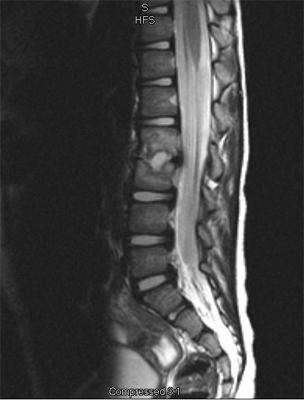

An MRI may be required if further examination of the spine is needed. An MRI machine uses magnetic waves, not X-rays, to show the soft tissues of the body. These tissues include the spinal cord, nerves, and discs. It can also evaluate spinal bones. An MRI allows your healthcare professional to look at slices of the area in question. The test may require the use of dye in an IV. Sedation or anesthesia may be needed to help your child lie still for this test.

In the early stage of the injury an X-ray may not show a fracture. Special imaging tests such as magnetic resonance imaging (MRI), computed tomography scans (CT), or a bone scan may show signs of a stress fracture. Spondylolysis may cause pain in a particular spot in the low back and spasm of the muscles along the spine. Often it will cause pain into the buttocks or thighs. Spondylolysis will often heal with the appropriate rest, a change in activity levels, and by avoiding hyperextension and rotation of the spine. Bracing may be helpful if symptoms do not get better.

Specific back pain means a structural cause for the pain is identifiable. Approximately 25 to 40 percent of children will have specific back pain and will show changes on imaging studies (such as X-ray or magnetic resonance images) that indicate a pathological reason (meaning one caused by disease) for their back pain. These causes include the following: